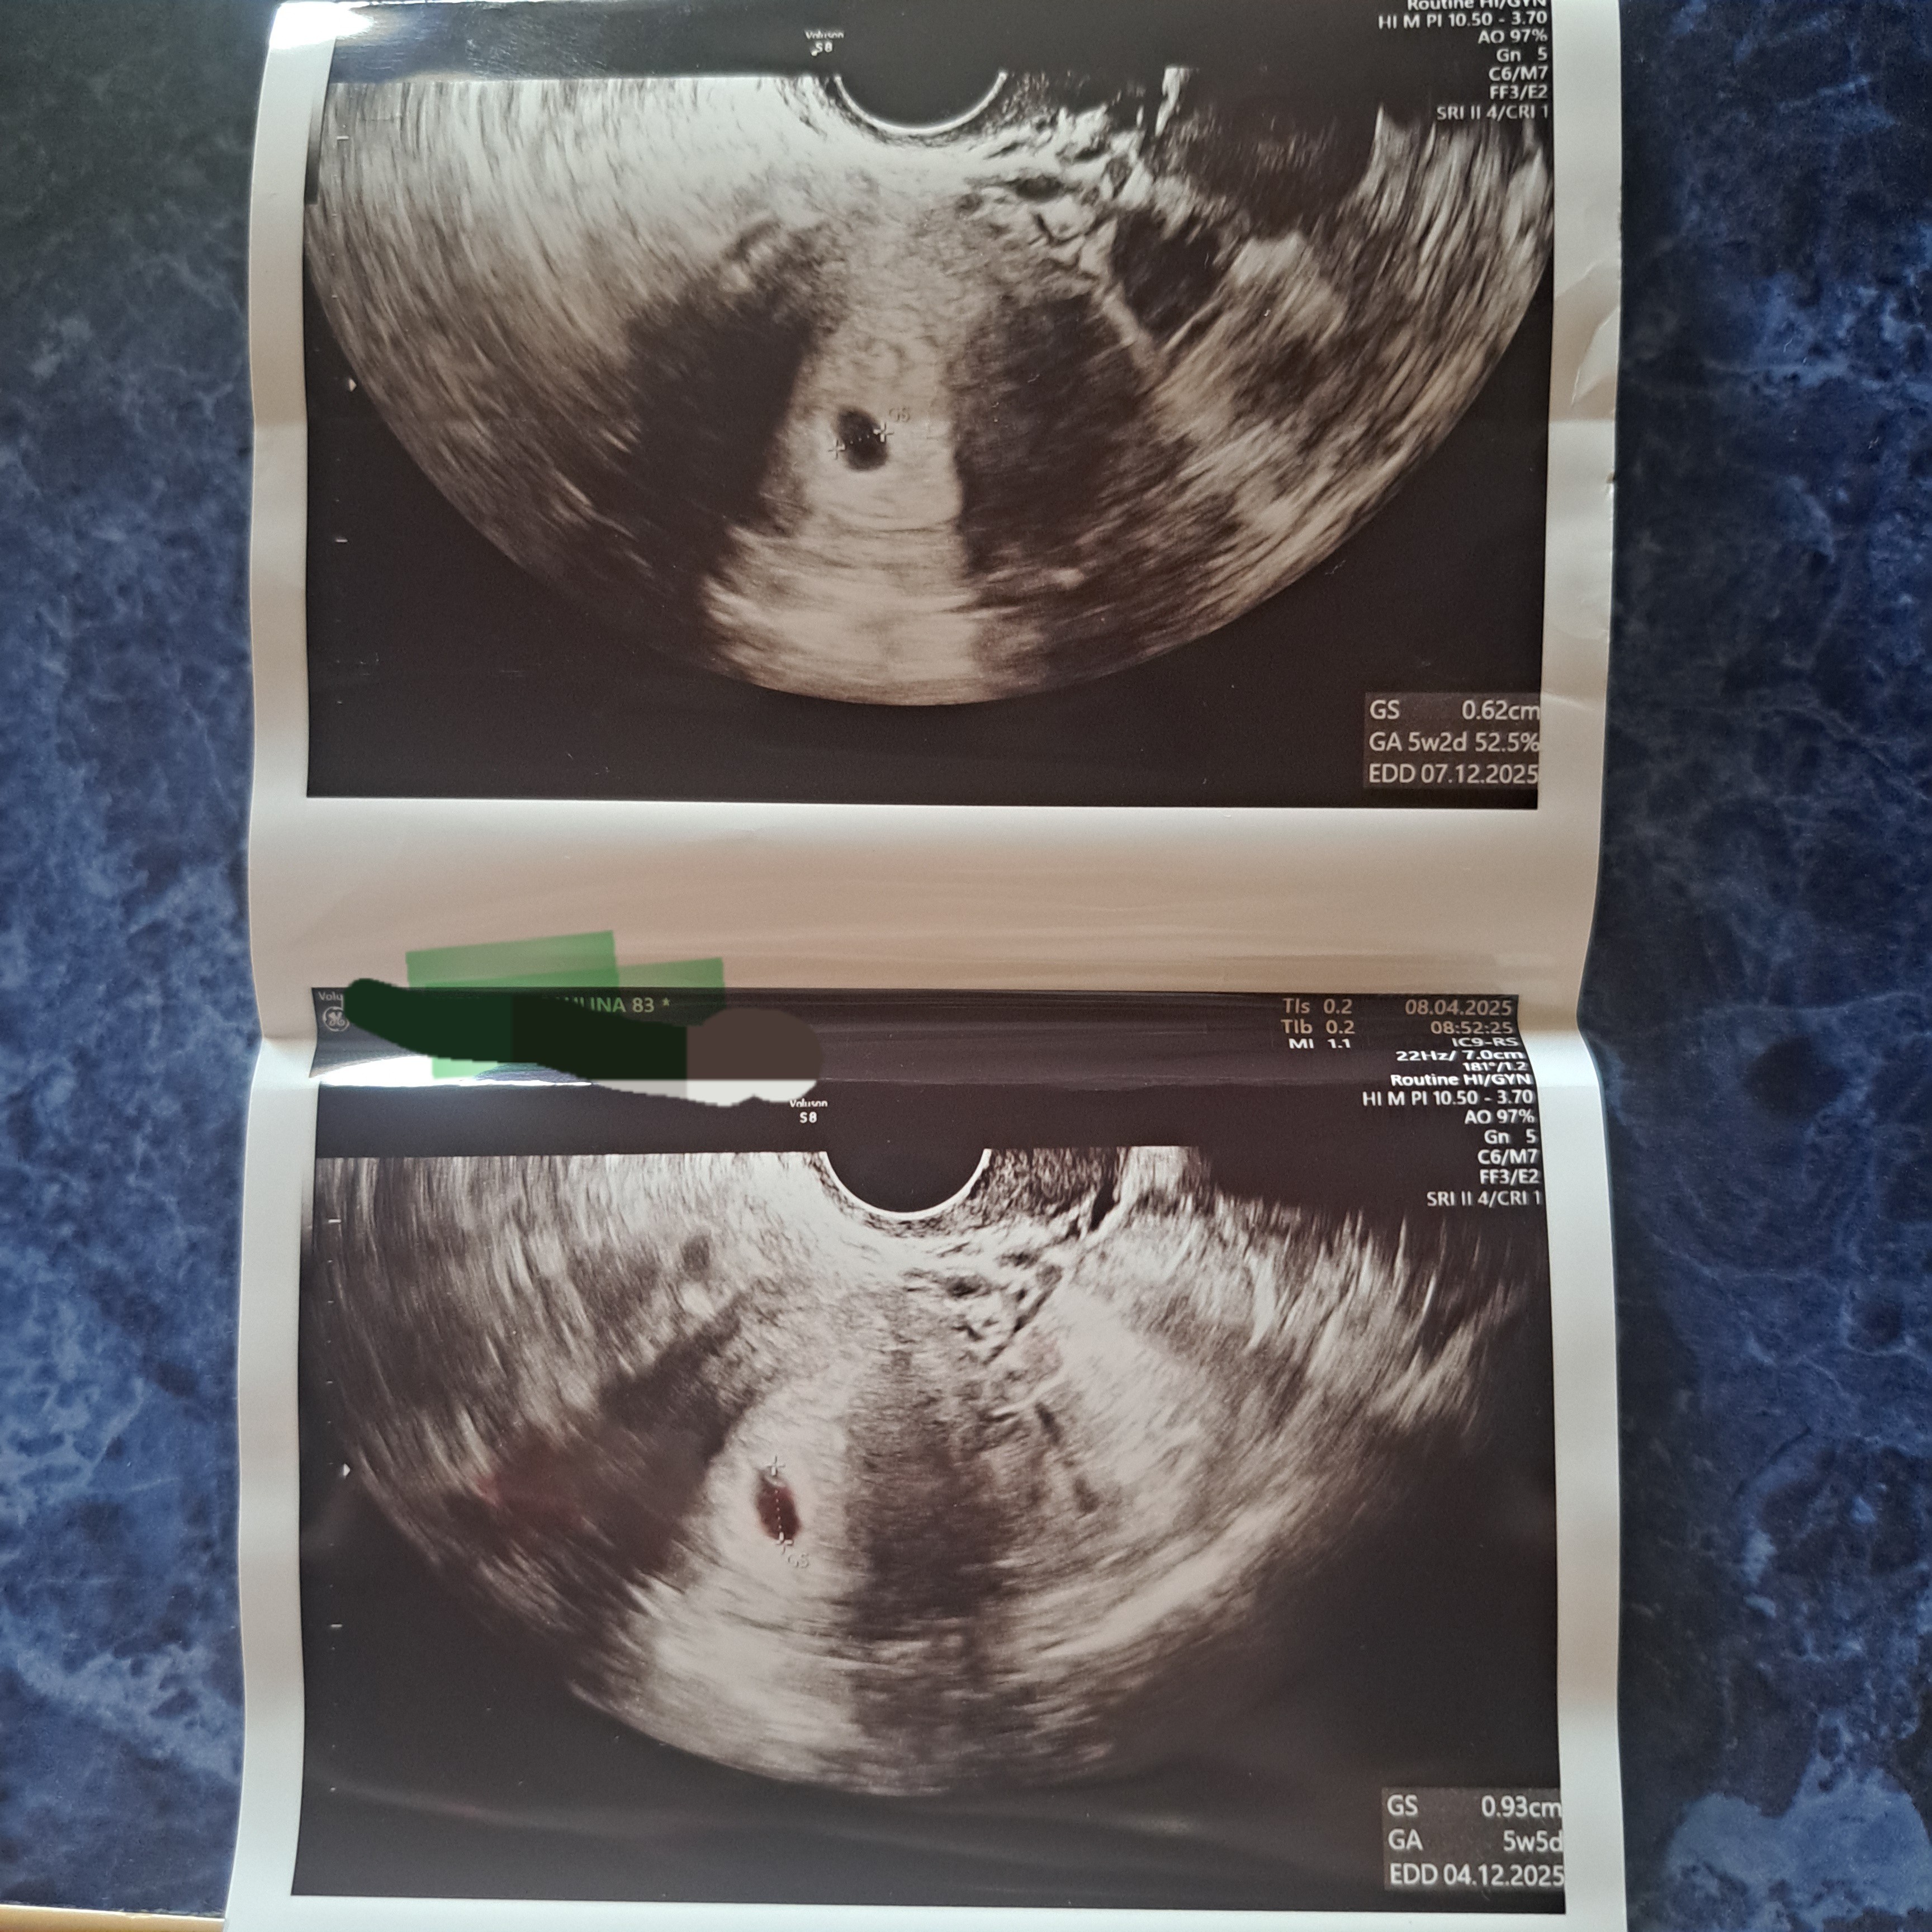

Pierwsze z wczoraj drugie sprzed 2 tyg.

W moim totalnie laickim oku też widzę, że w tym pęcherzyku jest jakby pęcherzyk żółtkowy. Ale ... On wydaje się być bardzo duży w porównaniu z pęcherzykiem ciążowym. Dodatkowo pęcherzyk ciążowy ma niereguralny kształt. Tylko, że to jest zdjęcie. Ciężko powiedzieć czy w obrazie faktycznie też tak wyglądało i nie są to jakieś złudzenia optyczne.

Generalnie jeżeli jest pęcherzyk żółtkowy to w max 3 dni powinien pojawić się zarodek. Rzadkością jest brak zarodka przy pęcherzyku żółtkowym